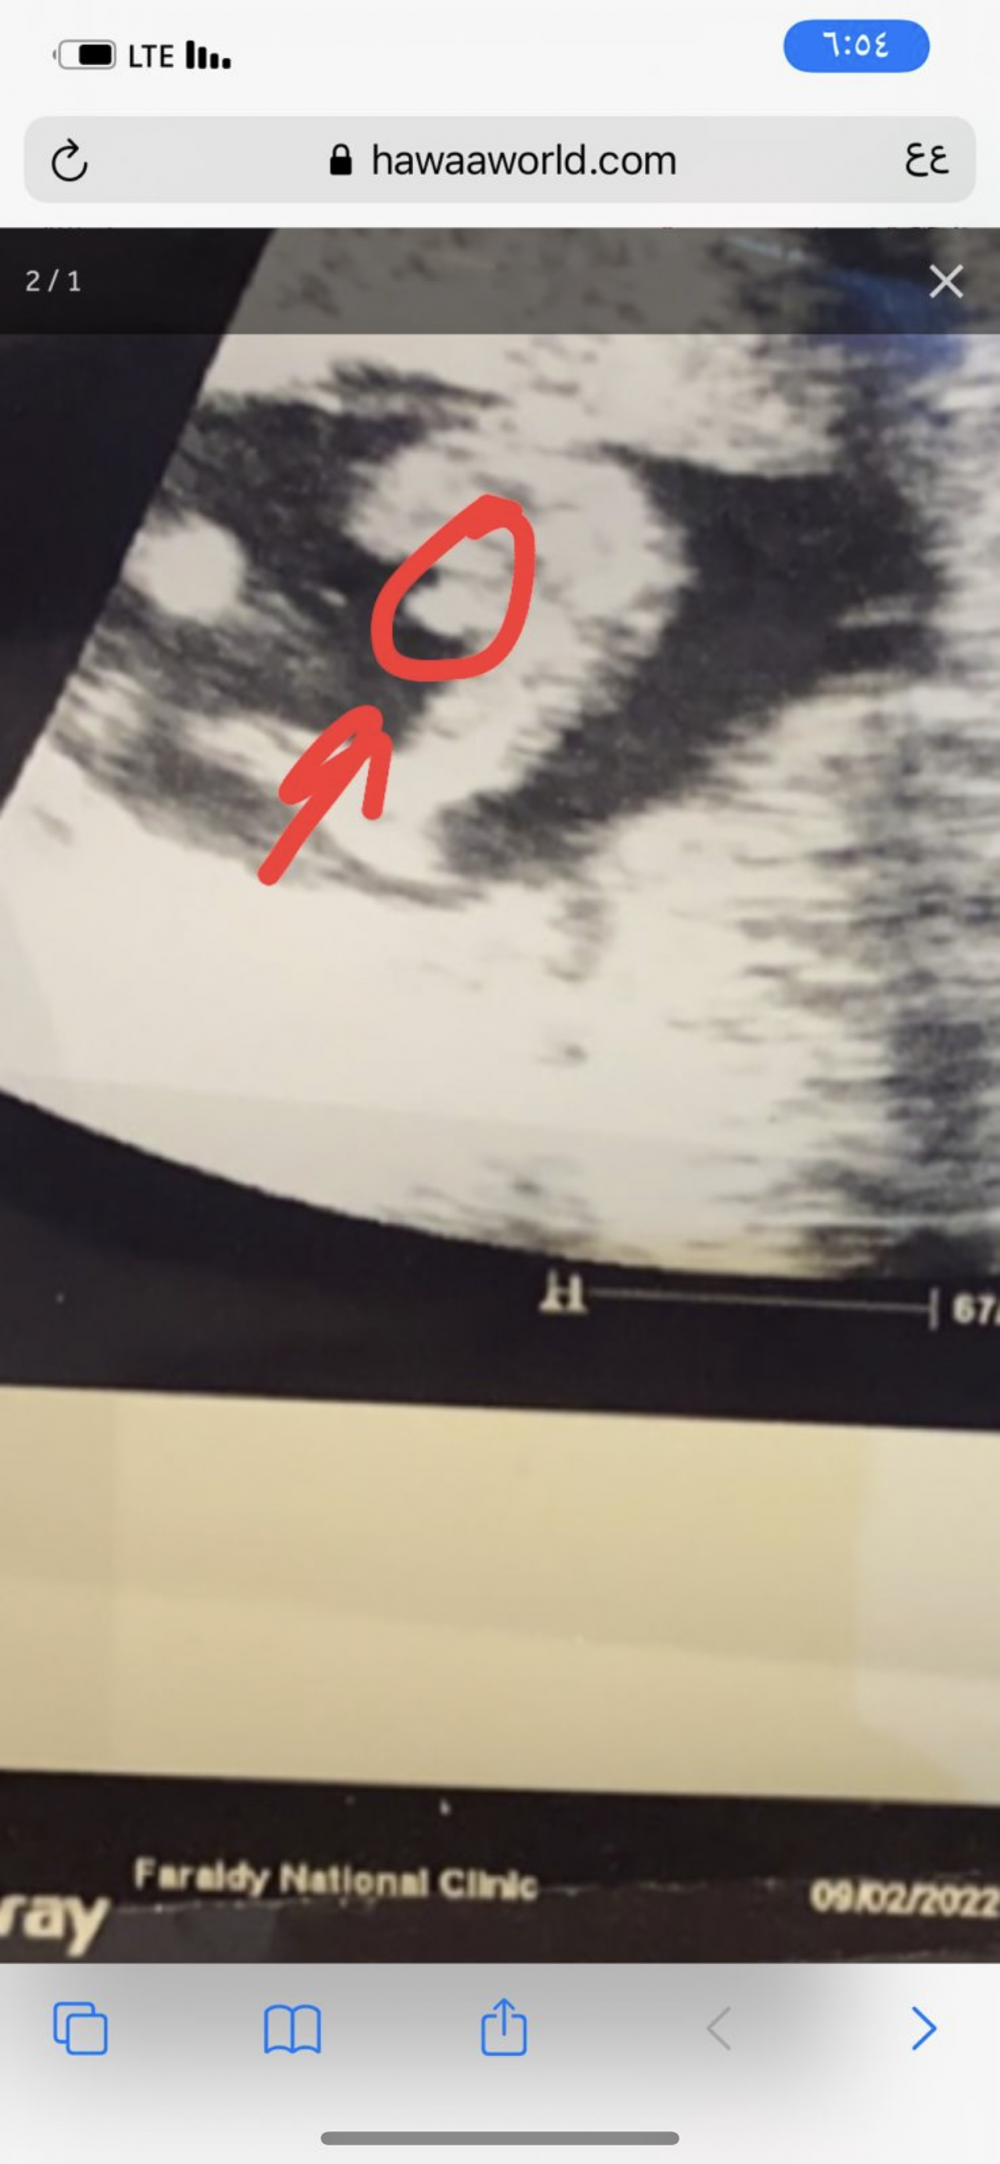

ماشاء الله واضح ولد الله يجيبه لك بالسلامة❤️❤️

في اولادي توريني الدكتورة العضو بس ما اقدر اميزه 🙈

المرة هذه ما ورتني شي ولا حتى نطقت الجنس

تقولي خمني🙄🙄 كأني صحبتها

ولما قلت لها بنت هزت براسها بالموافقه 😒😒